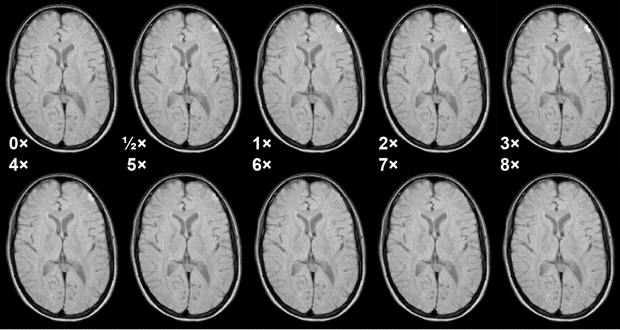

Figure 13-07:

Simulation of the influence of different tissue concentrations of Gd-based ECF space agents and mag­ne­tic field strength upon contrast in a glioblastoma. Strongly T1-weighted SE sequence, not field ad­just­ed.

Red curve = half dose; yellow = regular dose of 0.1 mmol/kg body weight; light blue = double dose; green = octuple dose.

The curves in Figure 13-07 correspond to the contrast between a glioblastoma and white matter af­ter enhancement. Before enhancement the contrast between glioblastoma and white matter is negative (the tumor is dark; its contrast behavior curve is below ½ dose but is not depicted in this figure) [⇒ Rinck 1999].

Only the regular (yellow) and double (light blue) doses give rise to sufficient con­trast at all fields. Increasing them is counterproductive (8x). Figure 13-08 shows this behavior in a meningioma.

Figure 13-08:

Simulation of the influence of different doses of a Gd-based ECF-space agent in a meningioma at 1.5 Tesla. Medium T1-weighted SE sequence. Note that at higher doses the T1 en­han­ce­ment ef­fect of the agent vanishes because T2 takes over. Best enhancement is seen at the re­com­mend­ed dose and double the recommended dose.

Simulation software: MR Image Expert®

The figures explain too that in most cases cutting the contrast dose is also counterproductive.